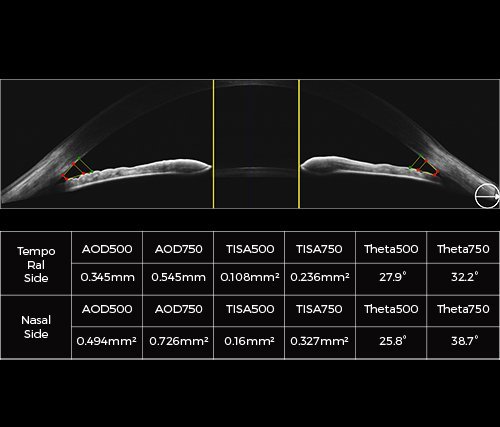

MOCEAN 4000

SLO-OCT e OCTA com VASCAN ADVANCE

O Mocean 4000 é configurado com os sistemas de imagens combinados SLO-OCT de ponta e o rastreador ocular baseado em SLO, uma plataforma poderosa para aplicações avançadas, como a angiografia OCT.